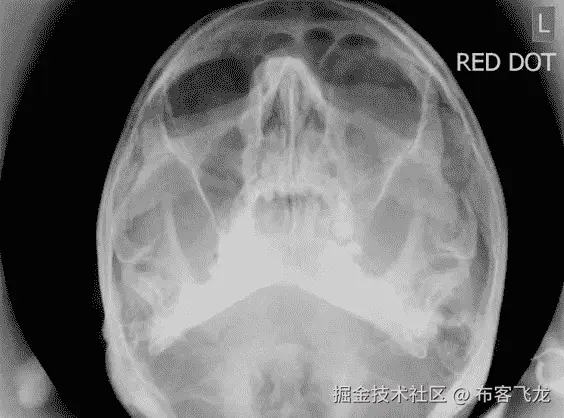

5.数字红点

很久以前,在放射学成为数字服务之前,放射科医生使用硬拷贝平片。这些二氧化硅和化学物质的薄片在黑暗的房间里被处理,挂湿晾干,然后被小心地放在棕色的文件纸条里,运送到阅览室。放射技师(技师)负责这个过程(不是放射科医师)。随着时间的推移,随着放射技师越来越熟练地阅读图像,开发了一种系统,放射技师将在胶片的角落放置一个小的圆形红色贴纸,以标记他们认为图像包含需要临床检查的病理。这个“红点”系统运行良好,尤其是在经验丰富的放射技师的监督下。红点胶片将被放置在报告堆的顶部,以确保当值放射科医师首先看到紧急的临床发现,反过来,病情最严重的患者将及时将他们的图像报告给相关的临床团队。

不幸的是,一旦引入数字 PACS,这种简单的警报系统就消失了。是的,放射技师可以数字标记图像,但通常情况下,图像仍然出现在报告队列中的正常位置。放射科医师在他们的阅片 PACS 中实际打开它们之前,不知道哪些胶片包含病理,哪些不包含病理。

Digitally annotated ‘red dot’ of a left orbital floor fracture. Note the annotation isn’t in fact red nor a dot, but it still does the job!.

我的第五家,也可能是最具临床价值的放射人工智能公司将开发一种数字红点系统,以实现早期分流。通过在简单标注为“正常”和“异常”的成像数据集上训练卷积神经网络,将建立一个简单的检伤分类系统,具有高异常敏感度但低病理特异性。紧急电影会出现在阅读清单的最上面,在不太重要的“正常”研究之上。

好处不言而喻——具有紧急发现的扫描将被报告并优先于“正常”研究采取行动。病人的安全将在一夜之间得到极大的改善。有报告积压的医院(即英国的每一家医院)可以更有效、更自信地首先处理重要的扫描,潜在地将癌症和其他等待列表减少几个数量级。成本节约潜力巨大。最令人兴奋的是,这样一个系统将为开发病理分类器奠定基础,让我们最终能够一瞥解释医学图像中病理的人工智能的开端。